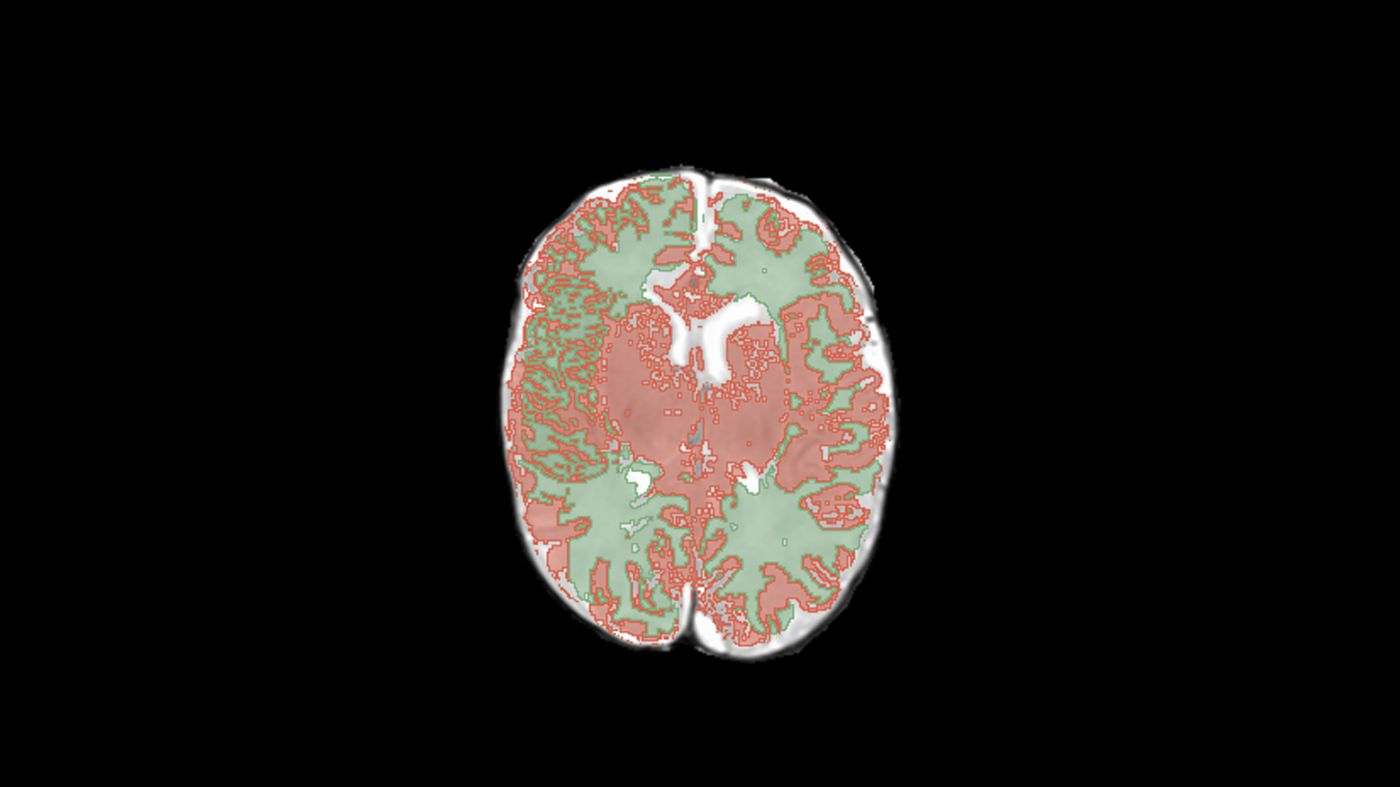

Example output from the algorithm

The solution automatically identifies gray matter and white matter areas on each MRI slice, providing predictions with confidence scores.

The service is primarily morphometric, meaning it measures tissue volumes. Once processing is complete, users see the model's predicted volumes of gray matter, white matter, and cerebrospinal fluid, along with descriptions of the largest structures.

\ From the summary table, you can select a specific study to view the scan with the white matter and gray matter masks applied.